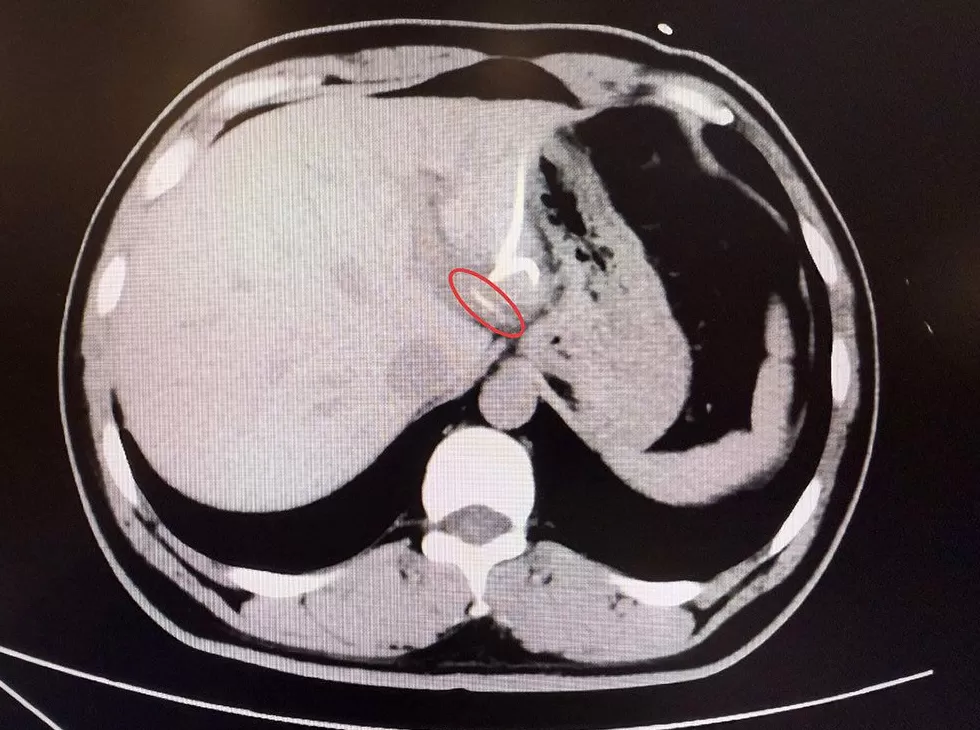

直到CT检查时,医生才惊讶地发现,李先生肝脏左叶靠近胃贲门处有一条细长的高密度影,形似鱼刺。原来,那根鱼刺在吞咽后穿透了胃壁,从贲门区域钻入肝脏,引发感染与脓肿。在简单进行肝脓肿介入穿刺引流后,当地外科医生评估后认为,要彻底清除异物,需要进行左半肝切除手术,但这对于李先生来说,创伤大、风险高,他难以接受。

患者李先生影像检查。本文图片均来自复旦大学附属中山医院